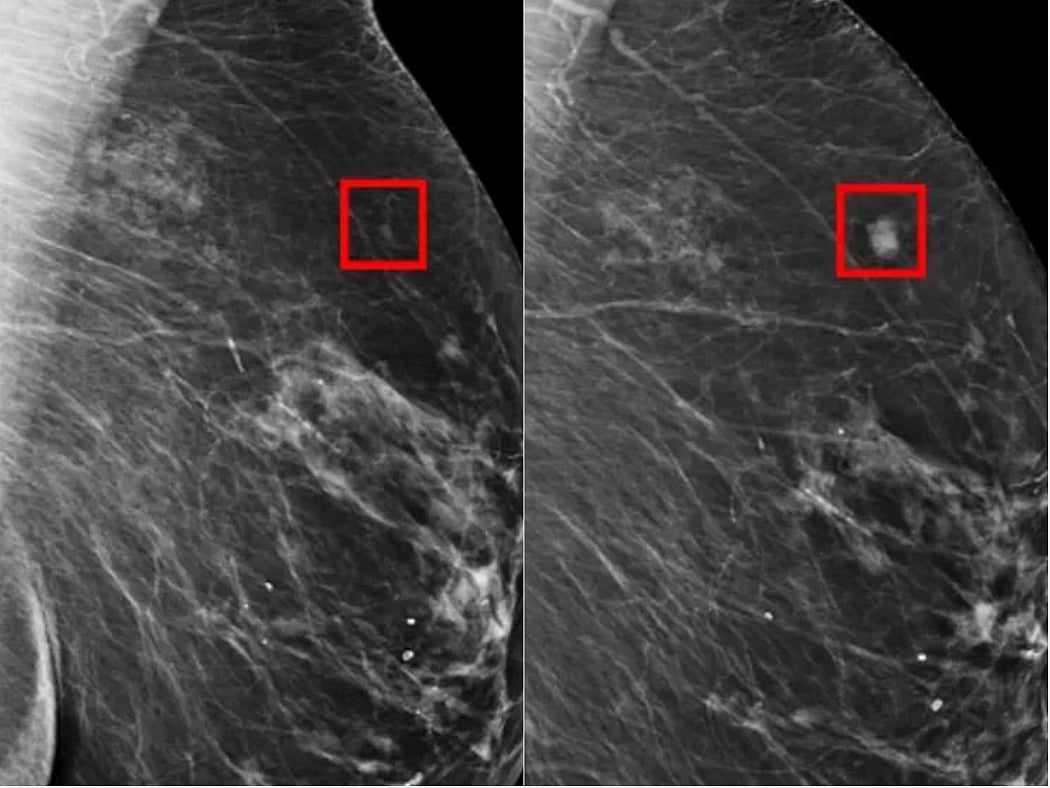

Artificial intelligence helps doctors spot more cases of breast cancer when reading routine scans, a world-first trial found Friday.

They were randomly sorted into two groups. In one, a single radiologist was assisted by an AI system to check the scans.

The other followed the standard European method, which requires two radiologists to read the scans.